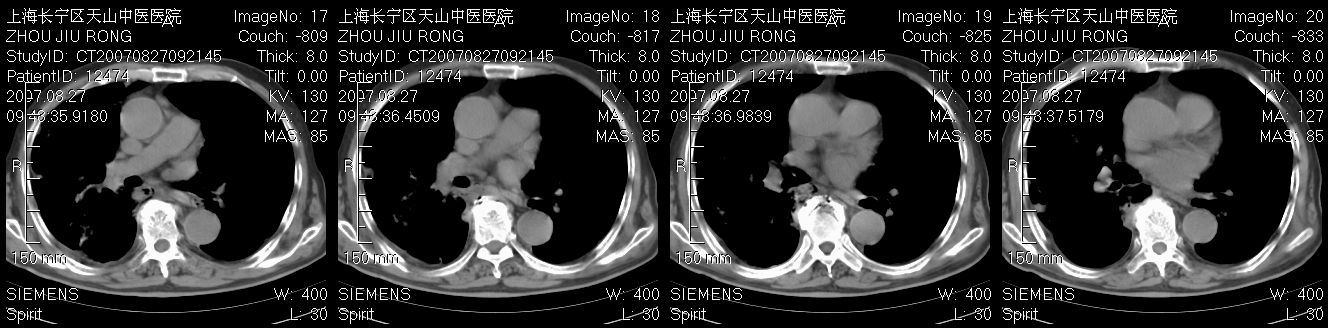

以下是引用zjzjr在2007-8-30 21:47:00的发言:[br]双肺弥漫性结节状、斑片状影,部分形成空洞,病灶以双肺上叶为著(符合结核发病部位),纵隔内见肿大淋巴结影。支持双肺继发性结核伴右上肺空洞形成。

以下是引用gaoshengjiang在2007-8-31 10:24:00的发言:[br]双肺弥漫性斑片状影及多发空洞影,其间夹杂多量条索状影,胸膜肥厚、粘连并有结节状改变,纵隔多枚淋巴结肿大,考虑1双肺继发型肺结核合并感染?2韦格氏肉芽肿?[br] 支持!